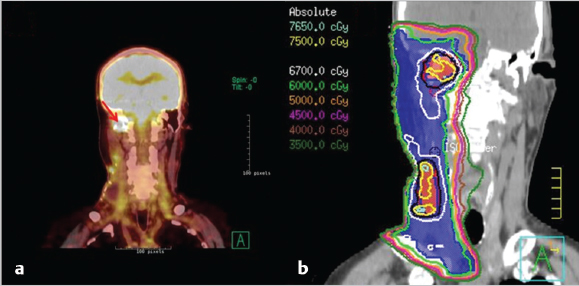

7 Role of Radiotherapy in the Treatment of Skin Malignancies Non-melanomatous skin cancers (NMSC), specifically basal cell carcinoma (BCC) and squamous cell carcinoma (SCC), are the most common malignancies in the United States. They are primarily managed surgically and carry an excellent prognosis, with a 1 to 5% rate of disease recurrence after complete excision and only exceedingly rare instances of distant metastasis. Historically, radiotherapy played a prominent role in the definitive management of these cancers as an alternative to surgical resection, especially in cosmetically sensitive areas. With the improvement in surgical techniques in recent decades, especially the widespread use of Mohs micrographic surgery (MMS), the use of curative radiation for skin cancers has declined. However, radiation is still commonly used in the definitive setting for patients with NMSC who are poor surgical candidates or have larger lesions in cosmetically sensitive regions of the face, and in the postoperative setting for more advanced tumors that have high-risk pathologic features that are associated with excessive risks of locoregional recurrence after surgery alone. Radiotherapy plays a similar role in the postoperative management of cutaneous melanoma. Radiation also offers excellent palliation for noncurable patients. This chapter reviews common indications, dose and fractionation schedules, techniques, and oncologic and cosmetic outcomes for radiotherapy for NMSC and melanoma ( Both surgery and RT can offer excellent cure rates for the management of early-stage NMSC. Surgery is typically the preferred method of treatment, given it can be performed in a single session, and has been associated with superior oncologic and cosmetic outcomes. One prospective randomized study compared the outcomes of MMS and definitive RT in 347 patients with less than 4 cm BCC of the face. The local failure rate was 0.7% for patients treated with MMS and 7.5% for patients treated with RT. Additionally, the cosmetic outcome was rated “good” or better more often in those patients who underwent surgery (87 vs. 69%).1 Though the technique of RT was not controlled (55% received interstitial brachytherapy and 45% received orthovoltage therapy), which could have affected the quality of the comparison, as the only randomized study, this trial remains pivotal in guiding medical decision making. A variety of factors can influence the decision to favor RT rather than surgery for NMSC. Typical contraindications to definitive RT include very large tumors and those with bone and/or cartilage invasion, given that control rates are typically inferior, as well as recurrent tumors that have been previously radiated or arise in an area of previous radiotherapy. Radiation should also be avoided in patients with genetic radiosensitivity syndromes, such as xeroderma pigmentosum and basal cell nevus syndrome, and in those with active connective tissue diseases, such as scleroderma and systemic lupus erythematosus.2 Patients who are candidates for definitive RT include those with unresectable disease, older patients with comorbidities limiting their surgical options, and patients with lesions involving the eyelid, canthi of the eye (especially those who carry surgical risk to the lacrimal duct), external ear ( Fig. 7.1 A modern linear accelerator, capable of delivering photon and electron radiotherapy with image guidance provided by cone beam CT (red arrow). A robust literature, much of it older when RT was more commonly used, supports the safety and efficacy of definitive RT for many of these aforementioned types of patients. A review of 986 BCC and SCC of the skin overlying the eyelid treated with definitive RT demonstrated a 5-year cure rate of 96.4%.3 A review of 334 BCC and SCC of the external ear at the Princess Margaret Hospital treated with definitive RT demonstrated a 2-year local control rate of 87%, with severe late toxicity noted in only 7% of patients.4 A review of 100 patients with SCC of the nasal skin at the Princess Margaret Hospital treated with definitive RT demonstrated a 2-year local control rate of 90%, with no severe toxicities observed.5 Fig. 7.2 (a) SCC of the helix of the left ear with bleeding (baseline). (b) After treatment with definitive radiation therapy (50 Gy in 20 fractions with electrons). There was complete remission with excellent cosmesis. Fig. 7.3 (a) A 96-year-old patient with right retroauricular BCC, T2N0M0 (baseline). (b) One month after treatment with definitive radiation therapy (50 Gy in 20 fractions with electrons). While definitive RT monotherapy can provide effective tumor control for T1–3N0 NMSC, T4 tumors and those with nodal metastases demonstrate inferior outcomes. Initial surgical management is recommended in these patients, often followed by adjuvant radiotherapy. T4 disease is defined as tumor invasion into the axial or appendicular skeleton or perineural invasion (PNI) of the skull base. The University of Florida reported a local control rate of just 53% at 5 years in patients with T4 BCC and SCC.6,7 In a review of 68 T4 BCC and SCC of the skin of the head and neck treated with definitive RT, local control rates were lower in patients with recurrent disease, compared to primary lesions (41 vs. 67%; p = 0.07) and the three most important prognostic indicators for inferior local control and cause-specific survival rates were bone involvement (p < 0.01), recurrent lesions (p < 0.01), and nerve involvement (p < 0.02).6 Even the more favorable lesions had local control rates of less than 70%. Similarly, a large retrospective review which included 531 BCC and SCC treated with definitive RT demonstrated local control rates of 94 and 89% for primary BCC and SCC tumors, respectively, and 86 and 68% for BCC and SCC recurrent tumors, respectively.8 In patients with nodal metastases, locoregional recurrence rates with definitive RT alone range from 30 to 50% and cancer-related mortality is as high as 30%.9 Such suboptimal outcomes support the use of intensification of treatment and multimodal therapy for these patients with advanced disease. In patients who are not eligible for initial surgical resection, concurrent cisplatin-based chemotherapy can be considered to enhance the effectiveness of radiotherapy. While there is no high-quality evidence demonstrating clear benefit to such an approach in cutaneous malignancies, many head and neck oncologists extrapolate from the mucosal SCC of the head and neck, where concurrent chemotherapy significantly improves disease control and survival in the setting of locally advanced disease treated nonoperatively.10 Fig. 7.5 A patient with multifocal BCC 3 months after treatment with definitive radiation therapy (40 Gy in 10 fractions with electrons). Postoperative RT is rarely used for BCC. Patients with BCC have an exceedingly low risk of recurrence after surgery alone, and even patients with a positive margin, focal cartilage invasion, or PNI are often still candidates for close observation and salvage re-resection if needed.11,12 However, postoperative RT is often considered in cases where there are persistently positive margins after multiple resections, T4 disease that extensively invades bone or soft tissue, lymph node metastasis, or clinically apparent PNI ( Postoperative RT is much more commonly used in resected SCC ( Retrospective data have demonstrated high rates of local recurrence in patients with T4 tumors managed with surgery alone.7 In addition, the rate of occult lymph node metastasis is high, ranging from 29 to 50%, in patients with advanced T-stage disease. In patients with deeply infiltrative (≥ 8 mm) tumors, or tumors that extensively invade deep subcutaneous fat, occult lymph node metastasis can be as high as 30%.9 Patients with recurrent primary tumors, PNI, lymphovascular space invasion, and those that are immunosuppressed are at significantly higher risk for having lymph node metastases and should undergo careful evaluation for regional disease with a contrast-enhanced diagnostic neck computed tomography (CT) and/or a positron emission tomography scan.14,15,16 In these patients, sentinel lymph node biopsy and/or neck dissection is recommended in conjunction with resection of the primary tumor. Postoperative RT can also be useful as an elective treatment to the undissected neck. Fig. 7.6 (a) A patient with right brow/forehead SCC (baseline). (b) One month after definitive radiation therapy (45 Gy in 15 fractions with electrons). Fig. 7.7 (a) An 88-year-old man with left temporal SCC in situ (baseline). (b) One month after treatment with definitive radiation therapy (30 Gy in five fractions with electrons). For patients with clinically involved lymph nodes, a therapeutic neck dissection followed by postoperative RT is the current standard of care. Although lymph node metastases are rare in SCC of the skin overall (~ 5%), they are clearly associated with a poor prognosis. After neck dissection alone, locoregional recurrence rates are 11 to 38% and even after multimodality therapy, the 5-year disease-free survival rates are 60 to 70%. Independent predictors of worse survival in this population include increased nodal size ≥ 3 cm, multiple lymph node involvement, extracapsular extension, incompletely excised nodes, and surgery monotherapy.15,16,17 A review of 167 patients in Australia with SCC metastatic to the parotid or cervical nodes compared outcomes for surgery versus combination of surgery and postoperative RT at a median dose of 60 Gy in 30 fractions. The use of postoperative RT was associated with significantly lower rates of locoregional recurrence (20 vs. 43%), and higher 5-year disease free (73 vs. 54%; p = 0.004), and 5-year overall survival (66 vs. 27%; p = 0.003) compared to patients who received surgery alone.16 Similar results supporting the benefit of postoperative RT for locoregional control and 5-year disease-free survival in patients with cutaneous SCC metastatic to lymph nodes and/or periparotid lymph nodes have been reproduced in a number of retrospective reviews.18,19,20,21 For patients who received lymph node dissection for primary SCC located on the trunk or extremities, postoperative RT is typically recommended when multiple nodes are involved or extracapsular extension is present. Similar to mucosal SCC of the head and neck, RT can be avoided in immunocompetent patients with a single involved lymph node, smaller than 3 cm, without extracapsular extension on parotidectomy or cervical lymph node dissection, as rate of regional recurrence is less than 5%.22 Fig. 7.9 A 91-year-old man with a history of extreme kyphosis and multiple facial SCC, who presented with a rapidly enlarging right neck mass, treated with surgical resection and free flap reconstruction. (a) Axial slice depicting isodose coverage of the neck bed with electron radiation therapy. (b) Extreme kyphosis dose coverage using 30 Gy in five fractions twice weekly. Fig. 7.10 A 63-year-old man with multiple recurrent SCC of the right temple with Mohs map overlying the site of the tumor. Fig. 7.11 (a) Coronal CT slice of dose distribution for postoperative radiation therapy after Mohs surgery for tumor depicted in PNI, while not common (5–10% of SCC), is another important risk factor for recurrence that should be weighed in the decision to administer adjuvant RT. PNI is typically divided into clinical and microscopic PNI. Clinical PNI is defined by neurologic manifestations, most commonly involving the trigeminal or facial nerves, leading to pain, paresthesias, paralysis, formication (the sensation of bugs crawling on the skin), or radiographic evidence of nerve enhancement.23,24 Microscopic PNI is appreciated only histologically and is identified after surgery in a patient who was asymptomatic preoperatively. PNI is important given it is associated with increased risks of local recurrence as well as regional and distant metastases. Factors associated with increased risk for SCC with PNI include male sex, tumor size greater than 2 cm, midfacial tumor location, recurrent tumor, and poorly differentiated subtypes.25 The degree of PNI is predictive of risk of recurrence; therefore, a careful history as well as physical and imaging examination is critical. Magnetic resonance imaging (MRI) has the advantage of identifying the extent of macroscopic disease through nerve enlargement or enhancement or obliteration of the normal fat plane surrounding a nerve ( The difference between clinical and microscopic PNI was highlighted in a series from the University of Florida which compared the outcomes of patients with PNI treated aggressively with surgery and postoperative RT. Those with clinical PNI had significantly lower 5-year rates of local control (57 vs. 90%; p = < 0.001) and overall survival (57 vs. 69%; p = 0.03) compared to those found to have microscopic PNI.13,23 RT is therefore always recommended in cases of clinical PNI. The role of postoperative RT in patients with pathologic PNI is less clear. Lin et al found that focal versus extensive microscopic PNI carries different prognoses, with relapse-free survival better in the former group (86 vs. 74%; p =0.1).24 Unfortunately, the distinction between focal and extensive was not well defined. As such, adjuvant RT is not recommended in immunocompetent patients with nonrecurrent disease, in whom one or two isolated areas of PNI are found in small unnamed nerves, with a diameter of less than 0.1 mm, given the outcome is expected to be fairly good with surgery alone. However, patients with microscopic PNI, that is multifocal, involves larger nerves (> 0.1 mm in diameter) and named nerves, or occurs in immunosuppressed patients, are at higher risk and thus adjuvant RT is recommended.2,25 For irradiation of clinical PNI, the clinical target volume should include areas at high risk of failure, specifically the involved nerve, the portion of the nerve proximally at the skull base, the distal skin innervated by the nerve, major communicating branches, and the compartment in which the nerve is embedded.26 For example, for patients with CN VII involvement, the area of treatment should be tracked back to the nerve’s exit through the stylomastoid foramen, with care taken to administer adequate coverage of the geniculate ganglion by avoiding excessive restriction of the radiation dose delivered to the ipsilateral cochlea. Similarly, with V1/V2 nerve involvement, the gasserian ganglion in Meckel cave and the cavernous sinus should be targeted ( Another consideration highly relevant to radiation field design is the observation that PNI may also be associated with increased nodal failure in addition to recurrence in the tumor bed and along the nerve pathway. Lin et al demonstrated that patients who developed recurrent disease with pathologic PNI had a significantly higher risk of local recurrence (40 vs. 19%; p < 0.01) as well as regional recurrence (29 vs. 5%; p = 0.02).24 It is important to consider the location of the lesion in such scenarios, given that tumors on the scalp, for example, may be less likely to metastasize to lymph nodes, compared to cheek, ear, or nasal skin lesions. Understanding the drainage patterns of these tumors is crucial (e.g., parotid nodes for head and neck sites, axilla for trunk and extremity lesions) and should be incorporated into radiation targeting. Fig. 7.13 (a) Axial radiation planning CT slice depicting inferior alveolar nerve (solid red) covered by isodose lines. (b) Axial radiation planning CT slice depicting left cavernous sinus and temporal musculature (solid light blue) covered by isodose lines. (c) Axial radiation planning CT slice depicting course of V2 into cavernous sinus (solid red) covered by isodose lines. (d) Sagittal radiation planning CT slice depicting coverage of V1 and V2 back to the cavernous sinus (solid red) covered by isodose lines. Fig. 7.14 (a) A 67-year-old man with history of recurrent right auricular SCC treated with multiple surgical resections and prior irradiation who presented with recurrent disease at the right skull base (red arrow). (b) Sagittal radiation planning CT slice depicting recurrent disease covered by 70 Gy isodose line (black line). Melanoma is believed to be a relatively radioresistant malignancy. Therefore, maximal surgical resection is paramount in the management of these tumors. RT has limited benefit in achieving long-term control in the presence of gross disease. RT is delivered to gross melanoma in patients deemed to have unresectable disease, or those with rapid postoperative recurrence who have failed surgical management. In these cases, higher doses per fraction are generally preferable and the intent of treatment is largely palliative. Adjuvant radiotherapy to the primary tumor bed, nodal basin, or both, has been studied as a means of reducing locoregional recurrence. If adequate margins are obtained, local recurrence for primary melanoma is infrequent, with rates consistently reported to be less than 5%.27,28 However, there is a smaller subset of patients with higher rates of failure in the tumor bed, including deeply invasive T4 disease, the presence of satellitosis, the presence of desmoplastic subtype, or persistently positive margins despite multiple attempts at excision. In these cases, adjuvant RT to the primary tumor bed should be considered ( O’Brien and colleagues analyzed 629 patients with head and neck melanoma and found that increased local recurrence rates were associated with increased tumor thickness: < 0.76 mm, 2%; 0.76 to 1.49 mm, 5%; 1.5 to 3.99 mm, 15%; and ≥ 4 mm, 20%.29 Typically, adjuvant RT is considered for T4 tumors, although typically reserved for those with additional high-risk features. One of which is satellitosis, which represents discontiguous sites of disease within 2 cm of the primary tumor and is known to be a marker of increased recurrence risk.30 Desmoplastic melanoma is a rare histologic subtype (1% of all melanomas) and is characterized by spindle-shaped cells with associated collagen production. This subtype is often associated with perineural spread and local recurrence rates have been reported as high as 20 to 50%.31,32 In these cases, based on the relatively higher risk for local recurrence, adjuvant RT should be considered. More extensive literature guides the use of adjuvant RT to nodal basins, both in the elective setting and following lymph node dissection.33,34 Data supporting the benefit of RT in reducing regional recurrence come from the randomized phase III study by Burmeister et al in which higher risk patients were randomized to surgery and lymph node dissection with or without adjuvant radiation to the nodal basin.35 Eligible patients had one of the following features associated with increased failure rates: 1. Serum lactate dehydrogenase < 1.5 times the upper limit of normal and the presence of extracapsular extension (ECE). 2. ≥ 1 involved parotid node of any size. 3. ≥ 2 involved cervical nodes and/or ≥ 3 cm of tumor within a node. 4. ≥ 2 involved axillary nodes and/or ≥ 4 cm of tumor within a node. 5. ≥ 3 involved inguinal nodes and/or ≥ 4 cm of tumor within a node, and/or recurrent disease.27,30 Importantly, no systemic therapy was delivered in this trial. In the 217 patients included on the study, those who received RT were significantly less likely to experience regional recurrence compared to those in the observation arm (18 vs. 33%; p = 0.041). As distant metastasis is the predominant mode of melanoma disease failure, it was not surprising that an improved rate of regional control did not translate into an overall survival average (54 vs. 44%; p = 0.12). The most common Grade 3 or 4 adverse events were seroma and wound infections, which were equivalent in both arms.35 The lack of systemic therapy in this study as well as the lack of a survival difference with the use of RT has raised the question of the true benefit of adjuvant RT for all patients eligible for this study. That said, it reinforces the guiding principle where locoregional control is a priority, and in a case with extensive nodal disease, especially with extranodal extension and significant soft-tissue involvement, adjuvant RT should be considered as a proven way to reduce rates of locoregional recurrence ( Fig. 7.15 A 72-year-old man with pT3N2cMx melanoma of the scalp with ulceration and satellitosis treated with wide local excision, free flap reconstruction, ipsilateral neck dissection, and adjuvant RT to the primary tumor bed. (a) Postoperative image. (b) Axial radiation planning CT slice demonstrating bolus material (red arrow) for achieving adequate surface dose.

Fig. 7.17,

Fig. 7.18, and

Fig. 7.19).